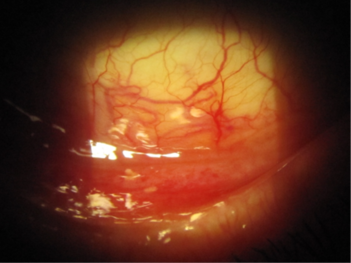

A 69-year-old female patient with unilateral POAG presented complaining of chronic conjunctival injection and irritation. Her condition was stable, based on serial visual field testing and OCT analysis of the optic nerves. Her IOP was 18mmHg with Goldmann applanation tonometry (GAT). Her glaucoma was being treated with latanoprost nocte in the left eye. On this last review she was found to have developed a cataract and was keen to explore her options for reducing or eliminating the drop burden on her ocular surface. Clinical examination revealed significant skin pigmentation and conjunctival injection of the left eye (Figs 1 and 2).

Fig 2. Significant conjunctival injection due to chronic prostaglandin use in the inferior fornix of the left eye

Cataract surgery was performed in combination with implantation of the iStent inject system in the trabecular meshwork. Her postoperative IOP was 14mmHg and the latanoprost drops were ceased in the left eye. Within a month there was a marked improvement in the appearance of her conjunctiva with resolution of the symptoms of irritation. Her forniceal conjunctiva ceased to be injected (Fig 3).

Fig 3. Image of the left conjunctival fornix indicating marked improvement in the appearance of the conjunctiva with resolution of the erythema